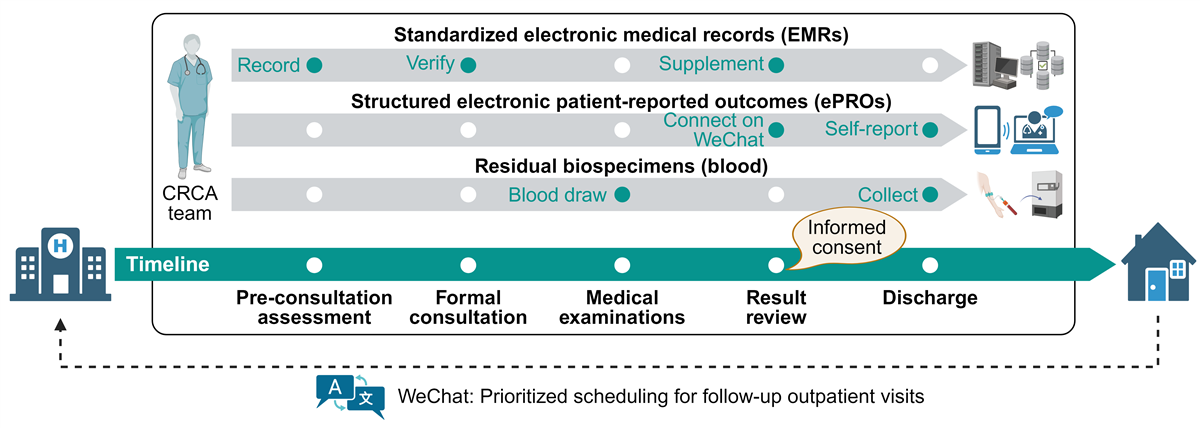

Emerging strategies enhance the feasibility and rigor of such an integrated model. Real-world evidence methodologies and symptom-driven phenotyping enable early identification of children with asthmatic symptoms, even before formal diagnosis [-]. Standardized electronic medical records (EMRs) improve data completeness and accessibility [,], while electronic patient-reported outcomes (ePROs) capture symptoms and experiences beyond clinical encounters [-]. In addition, residual biospecimens from routine testing can be repurposed for molecular endotyping using high-throughput omics technologies, minimizing invasive procedures [-]. These tools not only reduce cohort heterogeneity but also facilitate data harmonization and future integration, mirroring successful efforts in major birth cohorts [,].

In this study, we developed the Clinical Registry of Childhood Asthma (CRCA)—an outpatient-based integrated research platform that combines symptom-driven recruitment, real-world evidence collection, standardized EMRs, structured ePROs, and residual biospecimens. This framework supports both the establishment of a dynamically updated biorepository and enables phenotyping of early-life asthma. We aimed to characterize children across confirmed, suspected, and excluded asthma categories and identify factors associated with these diagnostic outcomes.

The CRCA is a prospective, longitudinal, digitally enhanced real-world cohort study launched on March 7, 2024, at the Respiratory Clinic of the Children’s Hospital of Chongqing Medical University—a tertiary pediatric referral center in Southwest China. Designed to address the critical gap in well-characterized outpatient cohorts for early-life asthma, the CRCA operates as an open, integrated research framework embedded within routine clinical workflows to enable long-term follow-up (). This manuscript presents a cross-sectional analysis of the baseline data from this ongoing cohort.

The term “digitally enhanced” refers to our core strategy of synthesizing two complementary data streams collected overtime: (1) hospital-based EMRs for structured clinical data and (2) smartphone-based ePROs for repeatedly capturing symptom and experience data from caregivers beyond clinical encounters. This dual-stream approach ensures comprehensive and continuous longitudinal data acquisition within a high-volume outpatient setting.

The CRCA study implemented a standardized EMR template to ensure consistent data collection. The baseline information module captured comprehensive demographic characteristics, including the child’s full name, date of birth, residential address, contact information, and body weight. The clinical assessment module systematically recorded medical data across multiple domains. These included respiratory symptoms, concomitant conditions, and current medications. It also captured treatment responses, physical examination findings, and laboratory results such as complete blood counts and allergen sensitization profiles (serum sIgE tests). Additionally, objective measures like lung function and fractional exhaled nitric oxide (FeNO) were documented. This module also documented complete medical histories, encompassing perinatal events, personal atopy history, previous severe pneumonia episodes, and mechanical ventilation history. Data were initially collected by research staff during preconsultation assessments, then verified and supplemented during formal consultations and test result reviews ().

Parents (primarily mothers) of eligible participants were invited to connect with the official WeChat account of the CRCA study. This account fulfilled 3 essential functions: establishing a direct pediatrician-parent communication channel for clinical inquiries, serving as the platform for ePROs collection, and enabling prioritized scheduling of follow-up outpatient visits.

Residual biospecimens (primarily blood) were collected by CRCA staff through the Clinical Laboratory Department, typically during the afternoon following blood collection. Samples were processed to isolate plasma, serum, peripheral blood mononuclear cells (PBMCs), and other blood cells. Serum and plasma were aliquoted at 200 μL per tube, PBMCs at 500 μL per tube, and other blood cells were stored in one tube per participant. All aliquoted samples were cryopreserved. PBMCs underwent programmed freezing. They were first stored at –80° C for over 12 hours before their final transfer to liquid nitrogen. All samples were ultimately categorized and stored under standardized conditions (–80° C freezers or liquid nitrogen) within our institution’s Biobank Center. All associated metadata were tracked electronically. This process followed protocols established by the Western China Birth Cohort study []. Residual blood specimens were not used in the present analysis to avoid purposeless consumption. However, the scientific value of these biospecimens is well-established. This is demonstrated by prior multiomics applications in Mycoplasma pneumoniae pneumonia research, which used identical specimen collection protocols [].